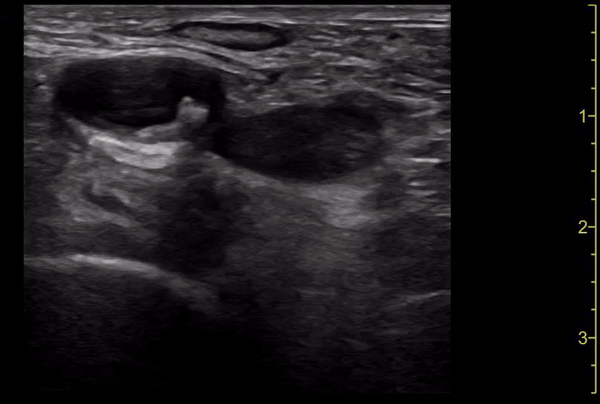

Clip 3: Deep vein thrombosis seen in right lower extremity